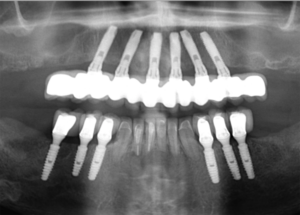

Figura 4 – Controle de um ano através de radiografia panorâmica da reabilitação inferior com implantes Cone-Morse Due Cone (Implaci De Bortoli, São Paulo/Brasil) e coroas unitárias, mantendo os remanescentes dentais do 33 ao 43 também como elementos unitários individualizados.